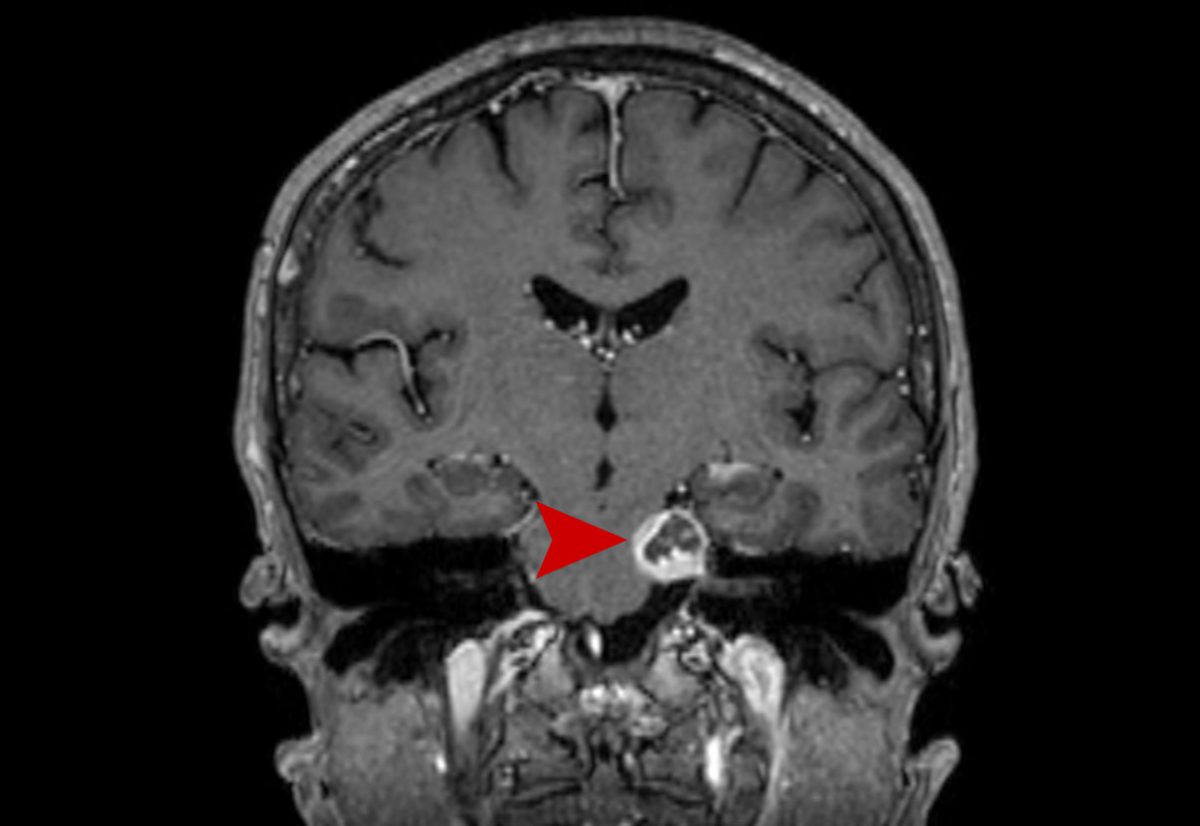

ήλυ 66 ετών με μηνιγγίωμα αριστερής Γεφυροπαρεγκεφαλιδικής Γωνίας και σύγχρονα πιεστικά φαινόμενα στο εγκεφαλικό στέλεχος. Σύγκριση MRI 11/2020 με 5/2021. Κεντρικού τύπου νέκρωση και σμίκρυνση της βλάβης.

Μετά την ακτινοχειρουργική θεραπεία με CyberKnife